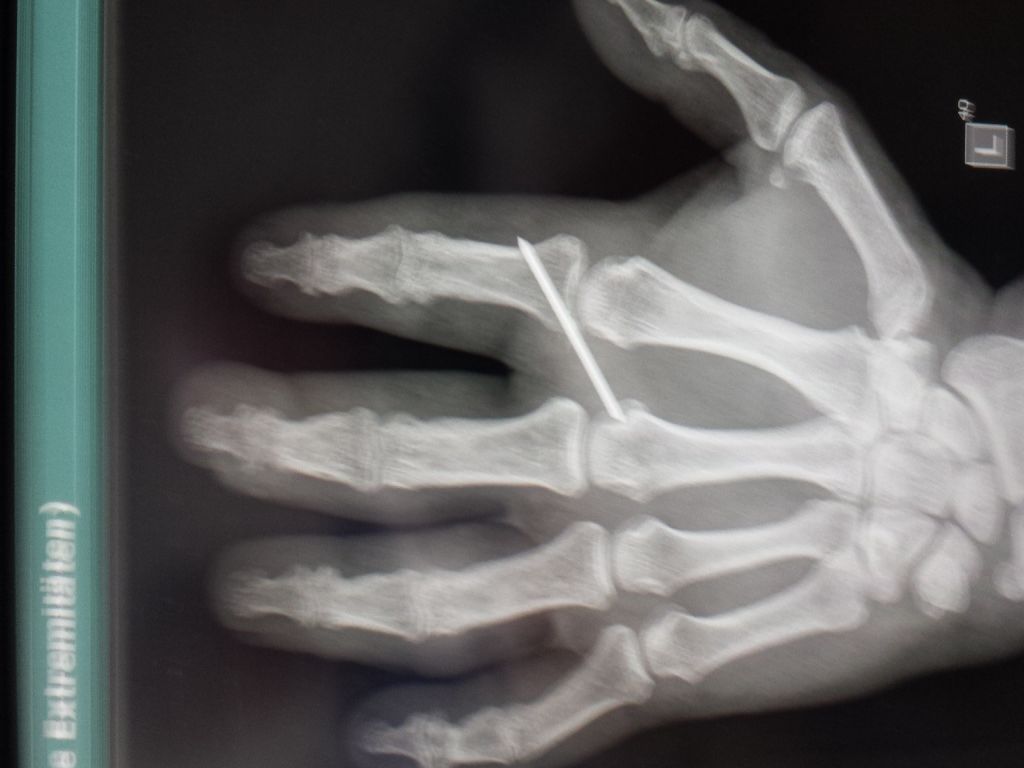

hast du eig. noch den Metallstift in deinem Finger?

War heute beim Oberarzt zum Nachsehen, sieht suuuper aus.

Nach seinen Worten hat er nicht damit gerechnet, dass es so schnell und reibungslos verheilt.

Nach dem Röntgen meinte er, dass einer Entfernung des Nagels nichts entgegensteht.

Dann fragte er mich, wenn ich Ihn raus haben möchte, ich sagte sofort morgen!

Das geht natürlich nicht, weil die op Pläne schon feststehen, aber Montag komme ich als erster Ambulant mit örtlicher Betäubung dran.

Ist nur ein ganz kleiner Eingriff meinte er.

Habe auch direkt ein Foto für Euch gemacht.

Boah Siggi, hast du schöne Knochen...

Aber irgendwas stòrt da auf dem Bild...